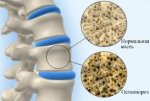

Остеопороз это особое заболевание, которое поражает костную ткань, образуя при этом пустоты-поры. В течении этой болезни кости всего скелета становятся очень хрупкими и при даже небольших нагрузках легко могут сломаться. Для больных, которые страдают этим заболеванием, стает проблематично открыть тяжелую стальную дверь или просто споткнуться, каждый пустячный эпизод заканчивается переломом.